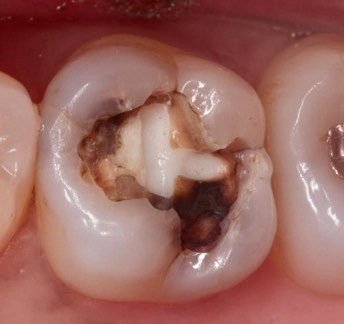

歯の内部まで進行したむし歯

小さな穴が開き、黒っぽく見える状態。

冷たいものや甘いものがしみるなど、自覚症状が出る場合もあります。